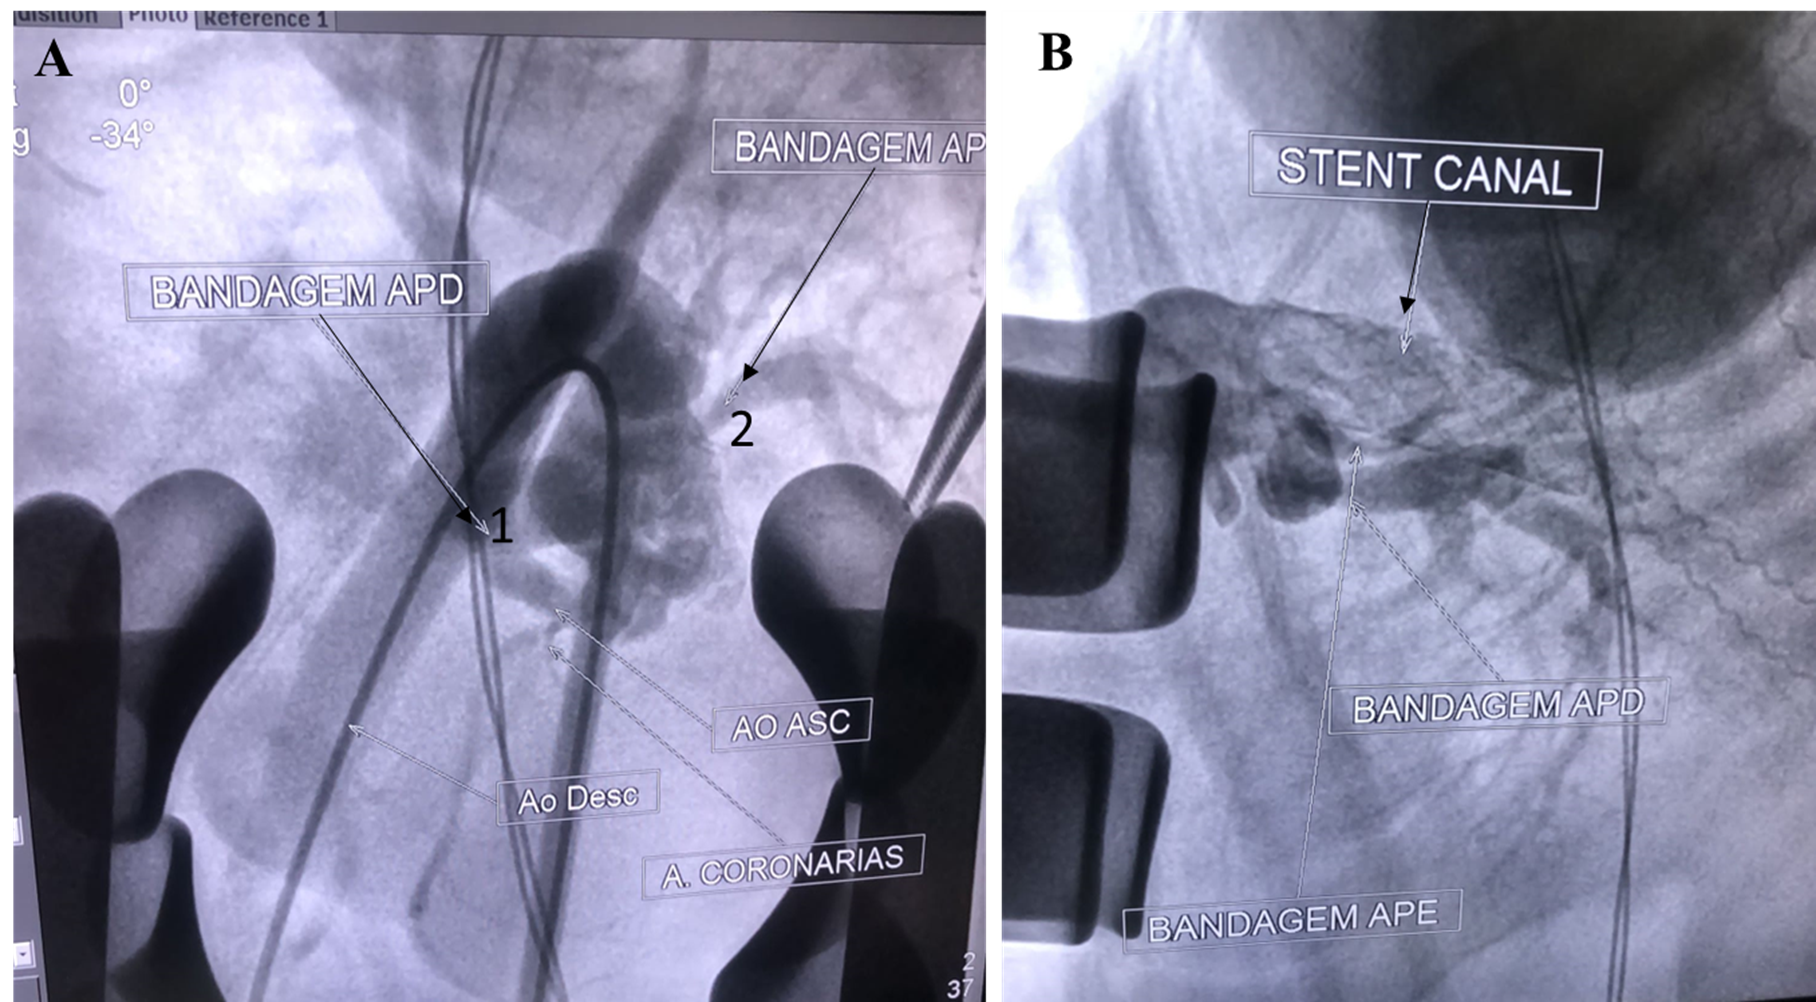

Stenting the Ductus Arteriosus of a Patient with Tetralogy of Fallot and Trisomy 18: Case Report and Updated Review

Márcio Erlei Vieira de Sá Filho, Marina Ayres Delgado, Bruno Vinicius Castello Branco, David Ribeiro do Nascimento